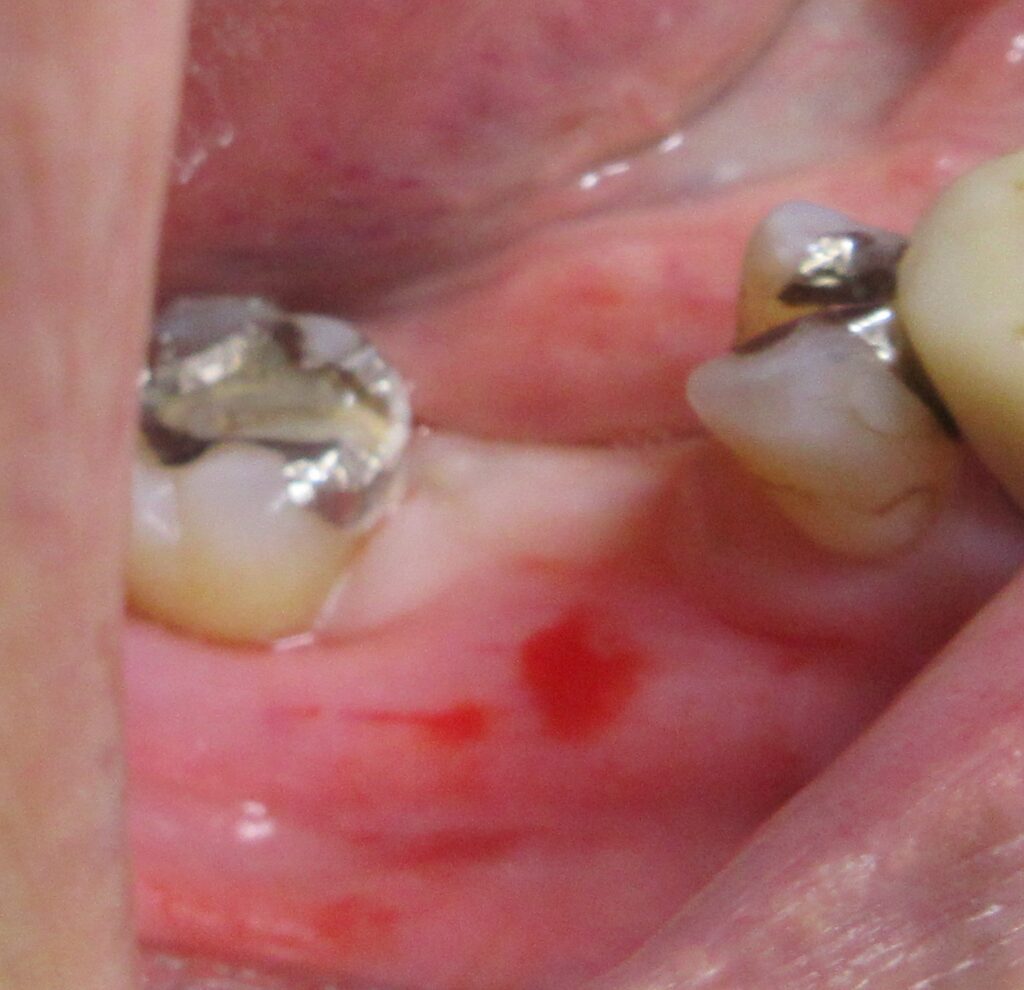

今回の患者様はインプラント植立を希望され、右下7番目の植立が決まりました。

当日の様子は、まず診療室に入っていただき、簡単にお口の中の全体的なお掃除と麻酔、仮歯を外す処置、CGFのための採血を行います。

麻酔が効いている事が確認されると、すぐにオペ開始です。

まずは歯茎から骨の部分までを穴開けパンチの要領で穴を開けていきます。

くりぬいた部分の歯肉を取り除き、次は骨に穴を開けていきます。